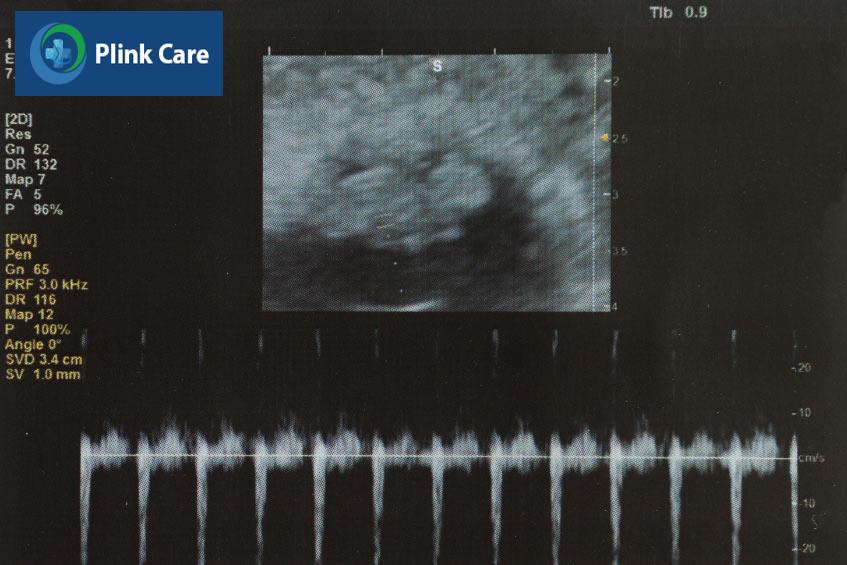

Bước vào tuần thứ 7 của thai kỳ, từ đầu đến chân của phôi thai có kích thước khoảng 10mm, nặng khoảng 0.8 gam, tương đương với kích thước của một quả việt quất (2). Kích thước của phôi thai trong tuần này đã to gấp đôi tuần trước, hình dạng chưa được hoàn thiện và rõ ràng nhưng đây là giai đoạn phát triển mạnh mẽ của phôi thai trong bụng mẹ.